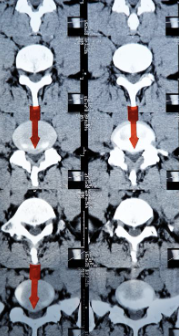

허리디스크는 디스크가 터져서 신경을 누를 경우 생기는 것으로 보통 4,5번에서 많이 발생하고 디스크가 터진 양이 적다면 터진 순간부터 수분이 날아가면서 양이 많이 없어지는데 그렇지 않고 양이 많을 경우 극심한 통증이 생깁니다.

허리디스크를 정확하게 진단하기 위해서는 엑스레이로는 힘들며, MRI를 통해 검사해야 정확하게 볼 수 있습니다.

MRI가 몸에 좋지 않지만 허리 통증으로 엑스레이만 진행할 경우 오진이 많아 지속적인 통증이 계속된다면 허리디스크를 의심하고 MRI 검사를 한번 받아보시길 권유드립니다.